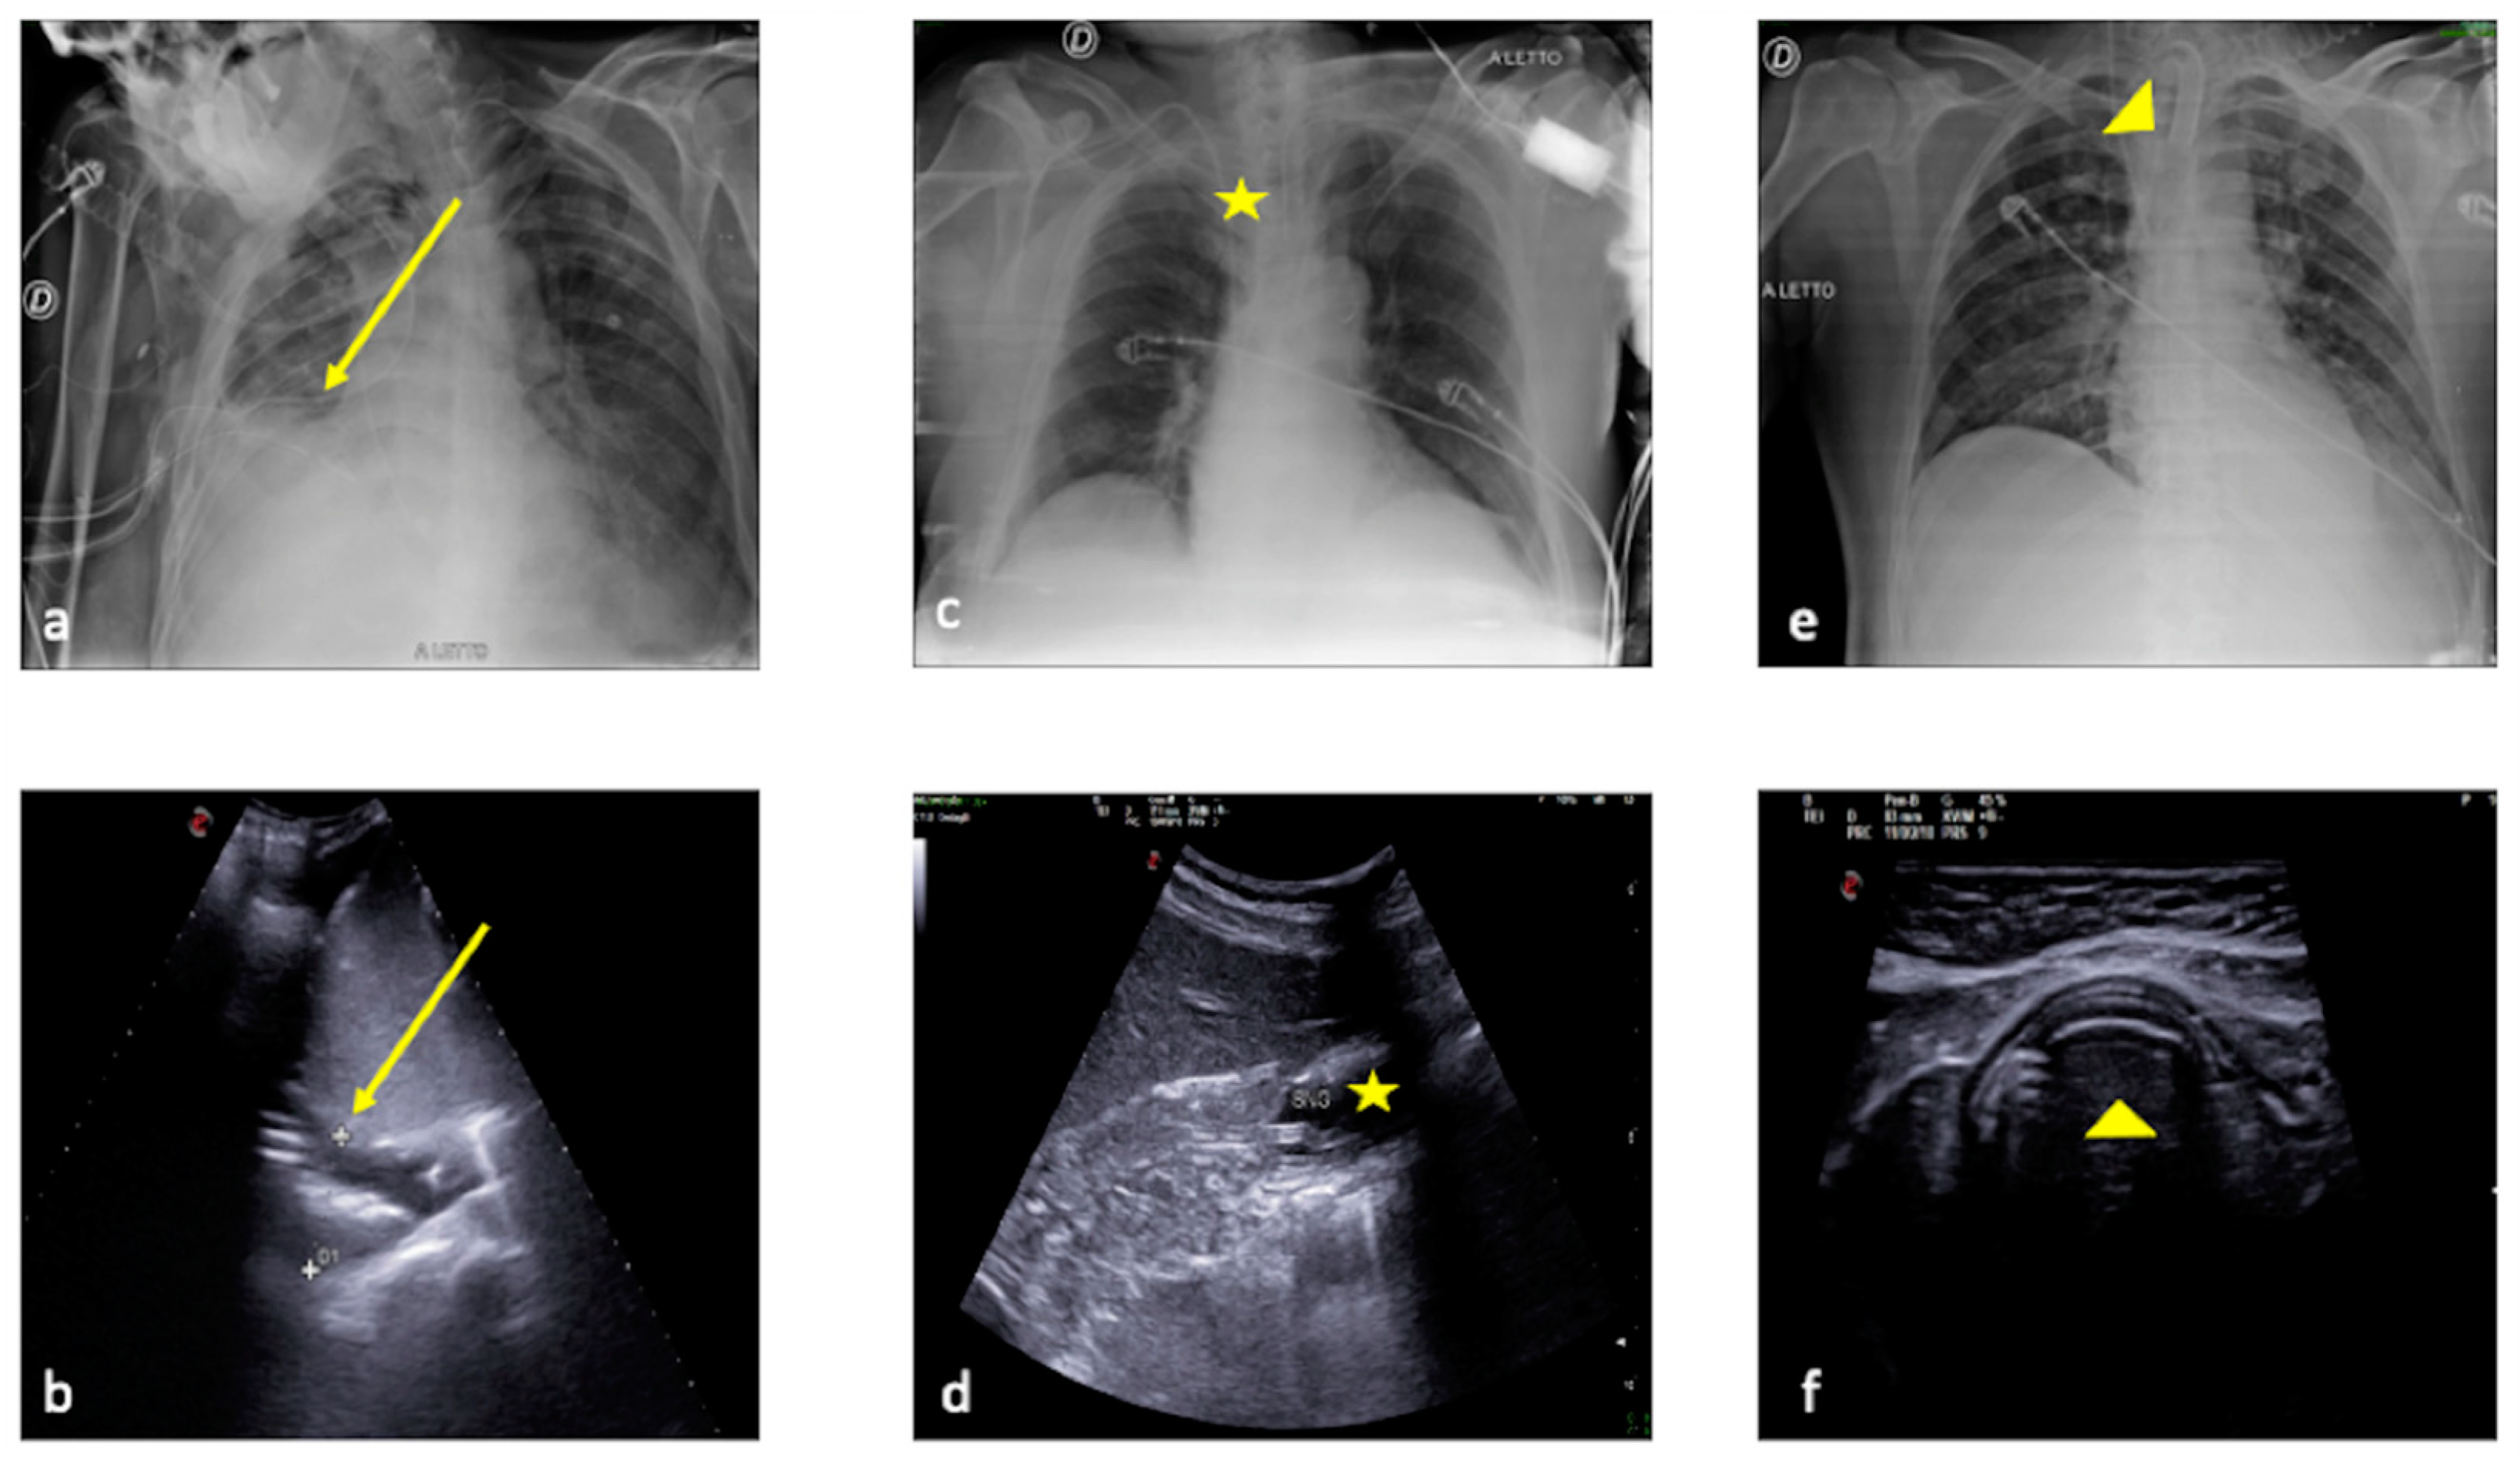

2.1. Atelectasis

2.2. Pneumonia

2.3. Pleural Effusion

2.6. Pulmonary Contusion

3. Confirming or Excluding Pneumothorax and Monitoring its Evolution